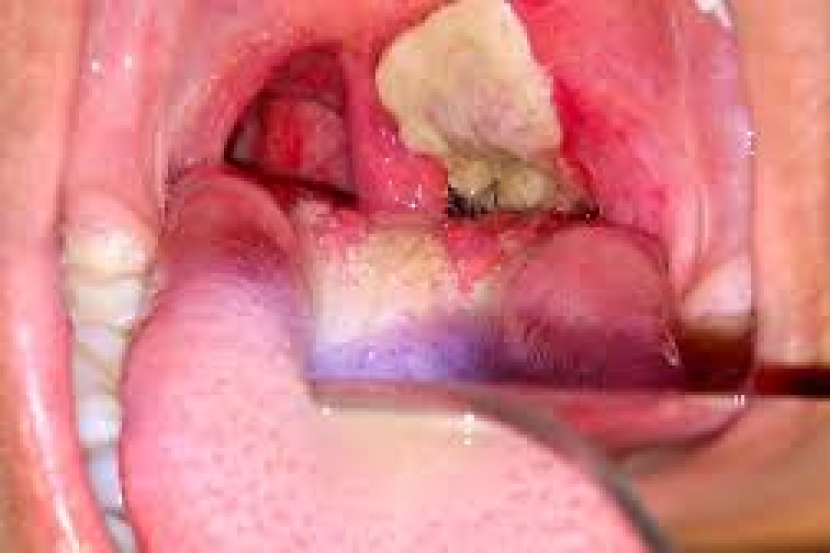

Beliau berkata difteria merupakan sejenis penyakit mudah berjangkit, dan bakteria penyebab penyakit itu mudah membiak di kawasan persekitaran yang kotor.